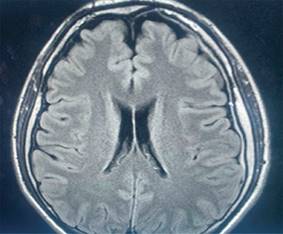

Además, se describen los hallazgos encontrados en la resonancia magnética (Figura 2).

Figura 2: Resonancia magnética. Hallazgos compatibles con hipotensión endocraneana con colecciones subdural frontal izquierda e interhemisférica, con realce paquimeníngeo y dilatación de senos venosos y venas corticales, sin evidencia de trombosis ni desplazamientos internos.